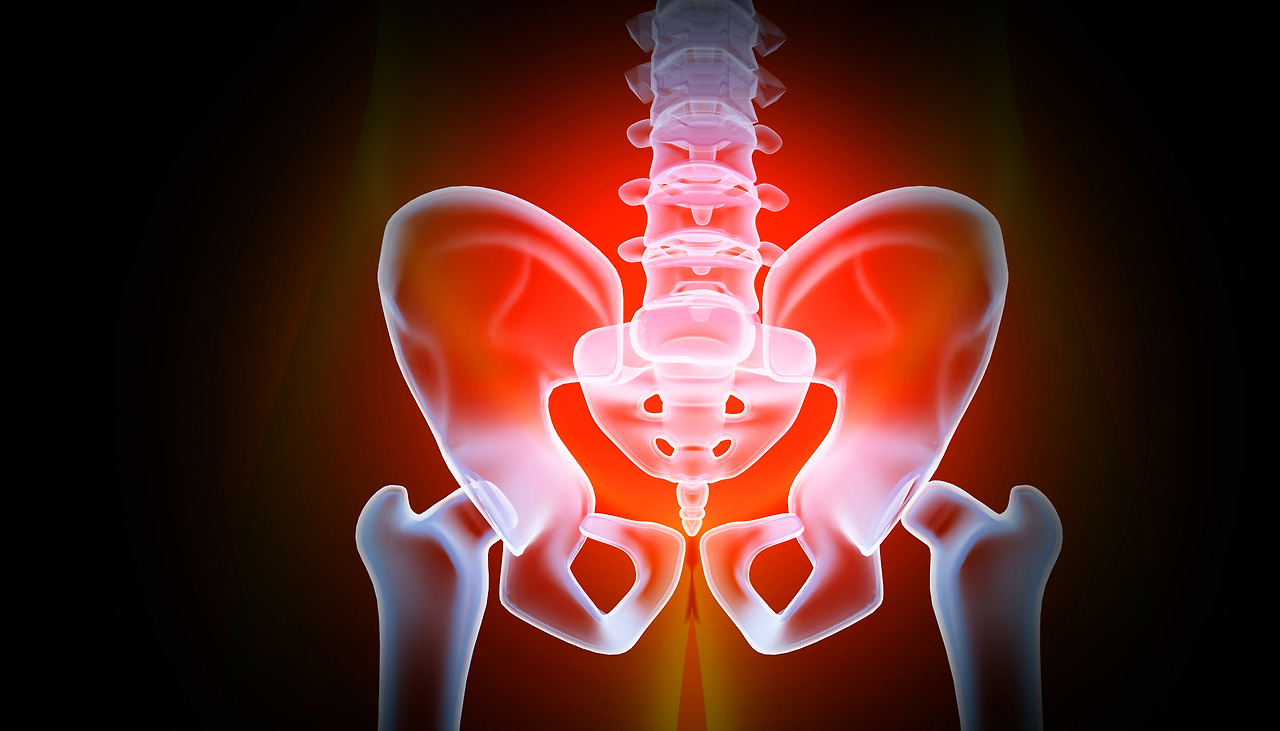

고관절 클리닉

● 담당: 일산백병원 정형외과 주석규 교수, 오형근 교수

고관절과 골반주위의 여러 병변즉 골관절염, 종양, 대퇴골두 무형성괴사, 고관절 기형 등을 특수 진단 장비를 이용하여 진단, 치료 합니다.